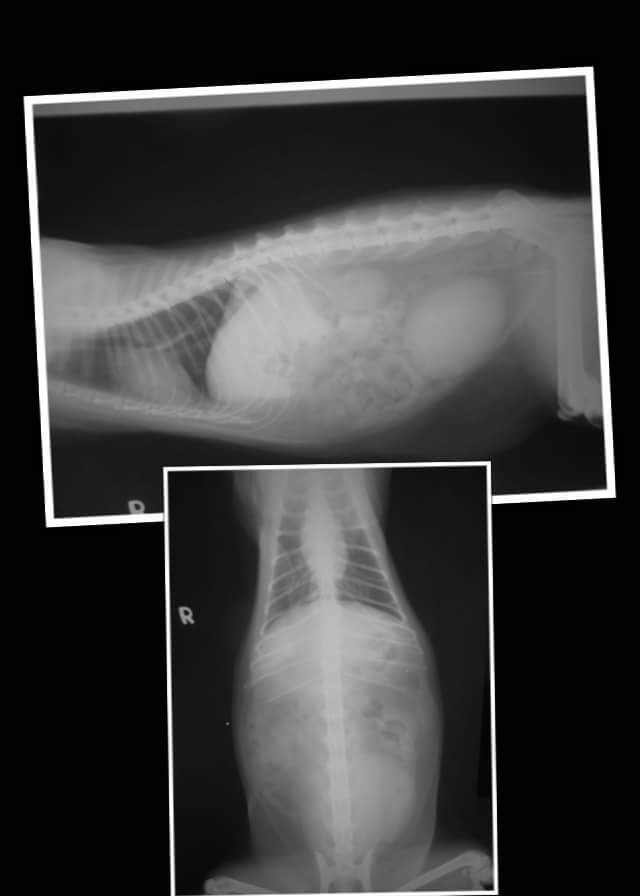

今天帶來的虎斑貓大虎,到院時有脫水,經血液檢查,其白血球及腎指數都過高,有尿毒症,腎衰竭的現象,左 腎有萎縮,此外貓二合一檢驗為貓愛滋陽性,目前已先給藥及輸液治療。

6.X光檢查 400*2= 800